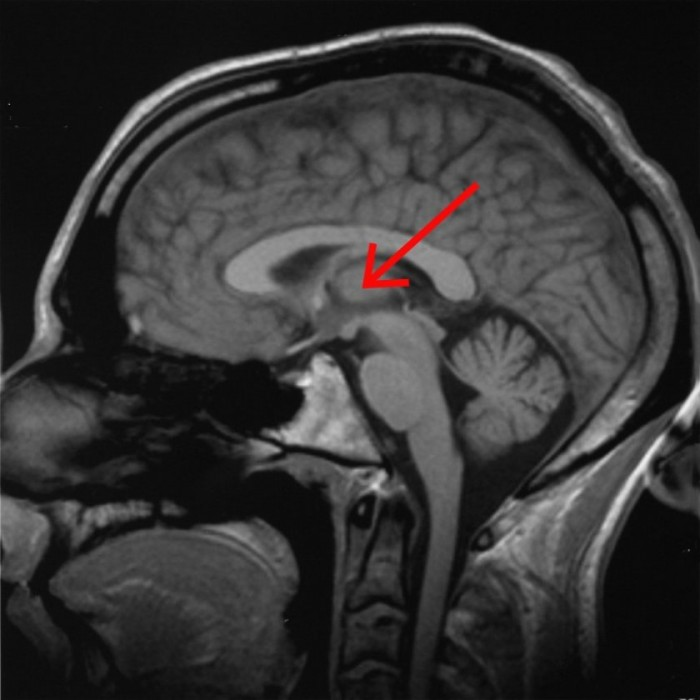

由上图可知,刺激的是这个叫 CL(central lateral nucleus)的区域。

这个区域在丘脑的什么地方?

central lateral nucleus 在丘脑中属于 intralaminar nuclei [2]

看这个图我们可以知道,intralaminar nuclei在丘脑内髓板internal medullary lamina 上就是两个小点儿。“须以50赫兹脉冲频率(即每秒重复50次)的电流同时电击仅仅相距20纳米的特定位置。”对比第一张的有效刺激位点,想必刺激的就是这两个小核团。所以,才会位置一旦偏移一些,wake的作用就没了。